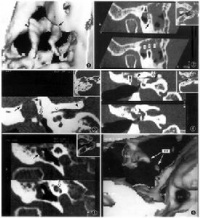

耳长期持续流脓,有特殊恶臭鼓膜松弛部或紧张部后上方有边缘性穿孔(图9-3)。从穿孔处可见鼓室内有灰白色鳞屑状或豆渣样物质,奇臭(耳部彩图10,11)。一般有较重传导

性聋,如病变波及耳蜗耳聋呈混合性。乳突X线摄片示上鼓室、鼓窦或乳突有骨质破坏区,边缘多浓密、整齐。

病理改变限于中、下鼓室粘膜病变侵蚀骨质,有肉芽及息肉,有胆脂瘤形成,耳流脓间歇流脓,粘液或粘脓性,不臭持续流脓,臭持续流脓,可有白色鳞片、豆渣样物,恶臭鼓膜紧张部中央性穿孔紧张部大穿孔或边缘性穿孔,可累及鼓环松弛部穿孔或边缘性穿孔听力传导性聋传导性聋或混合性聋传导性聋或混合性聋乳突X线摄片乳突多为硬化型,骨质无缺损破坏硬化型或板障型,有骨质缺损破坏有胆脂瘤空洞形成,边缘浓密锐利

慢性化脓性中耳炎--X光片

单纯型:乳突X线摄片常为硬化型,而无骨质缺损破坏。

骨疡型:乳突X线摄片为硬化型或板障型,伴有骨质缺损破坏。

胆脂瘤型:乳突X线摄片示上鼓室、鼓窦或乳突有骨质破坏区,边缘多浓密、整齐。